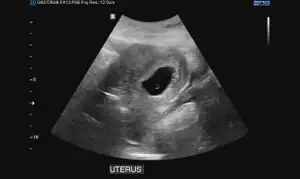

Obstetric ultrasonography may also be used to detect and diagnose pregnancy. It is very common to have a positive at home urine pregnancy test before an ultrasound. Both abdominal and vaginal ultrasound may be used, but vaginal ultrasound allows for earlier visualization of the pregnancy. With obstetric ultrasonography the gestational sac (intrauterine fluid collection) can be visualized at 4.5 to 5 weeks gestation, the yolk sac at 5 to 6 weeks gestation, and fetal pole at 5.5 to 6 weeks gestation. Ultrasound is used to diagnose multiple gestation.[3][19]